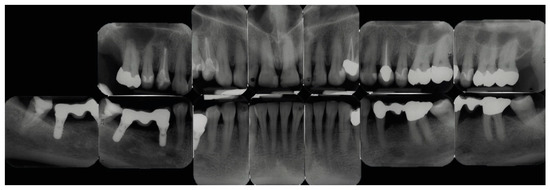

2.2. Radiographic Methods